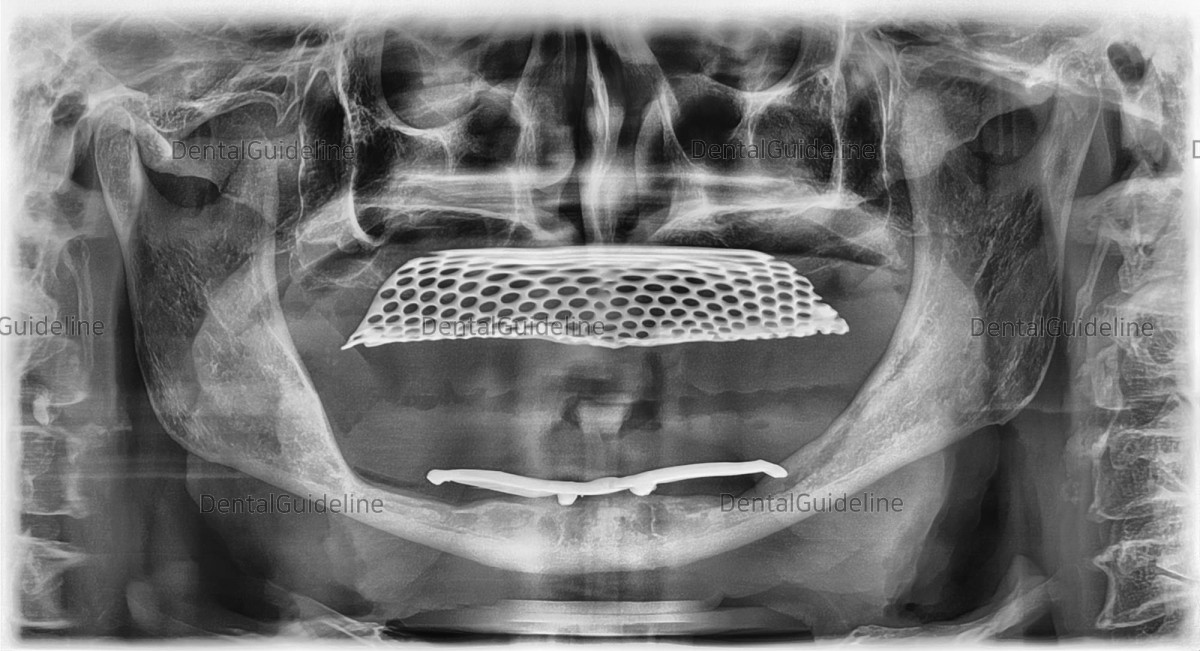

Why do edentulous patients need dentures?

By wearing dentures, not only functional but also minimal aesthetic recovery is possible.